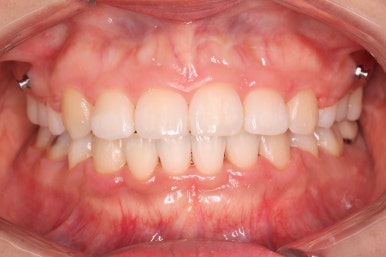

앞니, 어금니 맞물림이 좋아진 것을 볼 수 있습니다.

안으로 굽었던 옥니의 각도가 역교정으로 다시 회복이 되었습니다.

가장 눈에 띄는 점은 윗니를 후방이동 시켰기 때문에 돌출감이 있었던 부분이 개선이 되었다는 점입니다.

앞니의 간격이 있으면 위쪽 입술은 나와보이고 아래쪽 입술은 말려 들어가는 등으로 입술선이 부자연스럽다거나 심미적으로 좋지 못하는데 이 부분이 좋아졌죠.

특히 옆모습에서 부터 턱끝까지 이르는 S라인이 살아나게 되면서 입술선이 훨씬 예뻐졌습니다.

아랫니의 위치를 크게 변화시키지 않고 거의 윗니만 조절했음에도 불구하고 전체적으로 좋아졌죠.